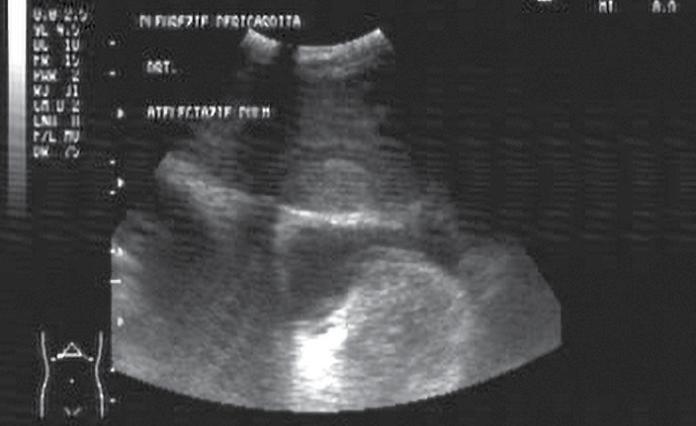

• contractilitatea globală a ventriculului stâng, identificând mărimea și statusul contractil – prezența unei insuficiențe cardiace acute (fig.2) cu necesitatea administrării medicației diuretice, inotrope, vasoactive în funcție de parametrii hemodinamici și corelarea cu aspectul plămânului și a venei cave; vizualizarea unui ventricul stâng hiperkinetic, cu reducerea volumui cavității (fig.3) ceea ce indică corelat cu aspectul VCI cu diametru redus (fig.4) o stare de hipovolemie ce necesită administrarea de fluide;

Fig.2. Secțiune subxifoidiană. Cord dilatat. Perete ventricul stâng redus în dimensiuni

Fig.6. Secțiune intercostală dreaptă. Colecție pleurală masivă. Atelectazie pulmonară de compresiune